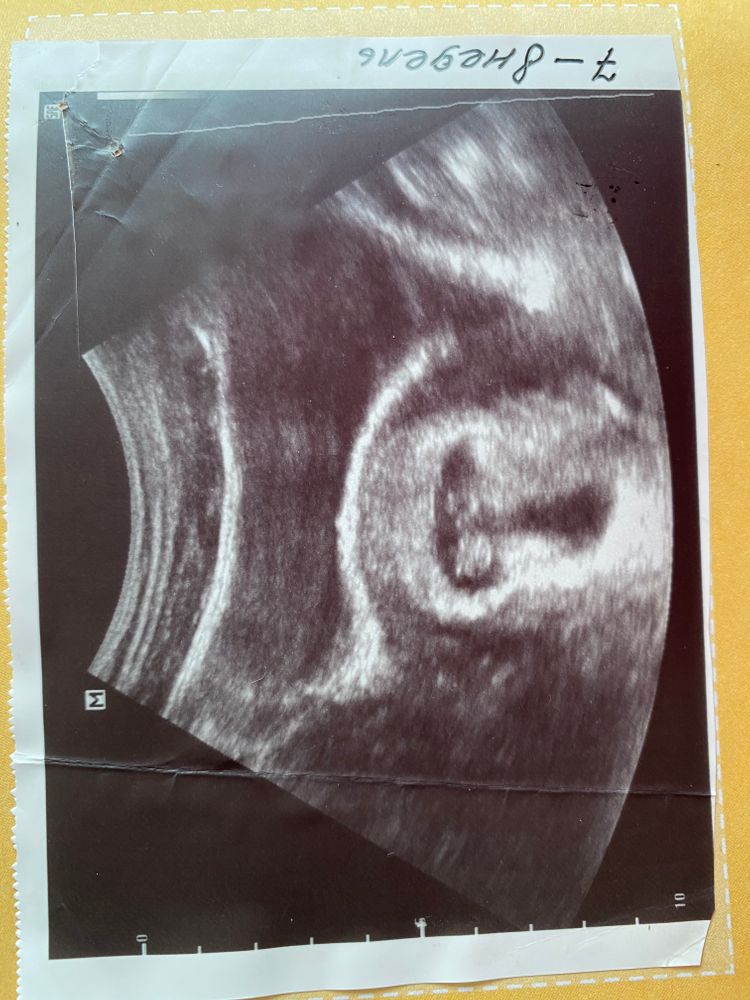

У вас не понятно ,по середине,а это мое УЗИ на 7 неделе  у меня не вагинальное по этому получается зеркально ,девочки слева мальчики справа ,вроде девочка на что я очень надеюсь ,позже проверим:)

у меня не вагинальное по этому получается зеркально ,девочки слева мальчики справа ,вроде девочка на что я очень надеюсь ,позже проверим:)

у меня не вагинальное по этому получается зеркально ,девочки слева мальчики справа ,вроде девочка на что я очень надеюсь ,позже проверим:)

у меня не вагинальное по этому получается зеркально ,девочки слева мальчики справа ,вроде девочка на что я очень надеюсь ,позже проверим:)

Короче долго я гуглила и по ходу похоже на мальчика😃 проверим, работает ли теория😏

Плацента позже формируется. По этому методу смотрят прикрепление хориона, не плаценты) По поводу пола не знаю, я в этом методе не разбираюсь, вечно путаю 😁

Чашка утреннего кофе, прикрепление не меняется. Сначала хорион, а потом станет плацента. Но на фото вообще не понятно где и что прикрепилось 🤭

Женечка, ну вообще да, по сути хорион и есть будущая плацента) Ничего непонятно - это да😅